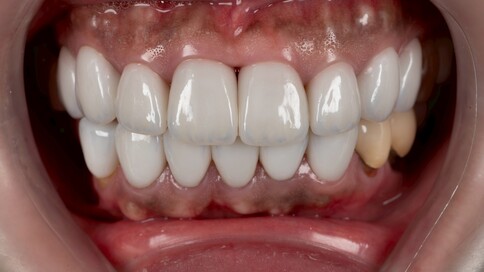

✨ 二、 兩顆的正中對決:對稱美學

Case 6:僅用兩顆全瓷冠解決色差與中軸偏差。